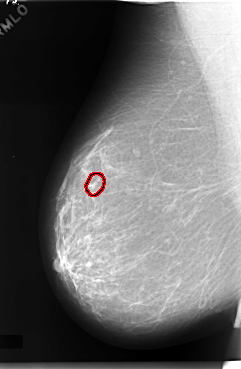

C_0057_1.RIGHT_MLO

RIGHT_MLO LINES 5904 PIXELS_PER_LINE 3856 BITS_PER_PIXEL 12 RESOLUTION 50 OVERLAY

FILE: C_0057_1.RIGHT_MLO.OVERLAY

TOTAL_ABNORMALITIES 1

ABNORMALITY 1

LESION_TYPE CALCIFICATION TYPE PLEOMORPHIC DISTRIBUTION CLUSTERED

ASSESSMENT 4

SUBTLETY 3

PATHOLOGY MALIGNANT

TOTAL_OUTLINES 1

BOUNDARY